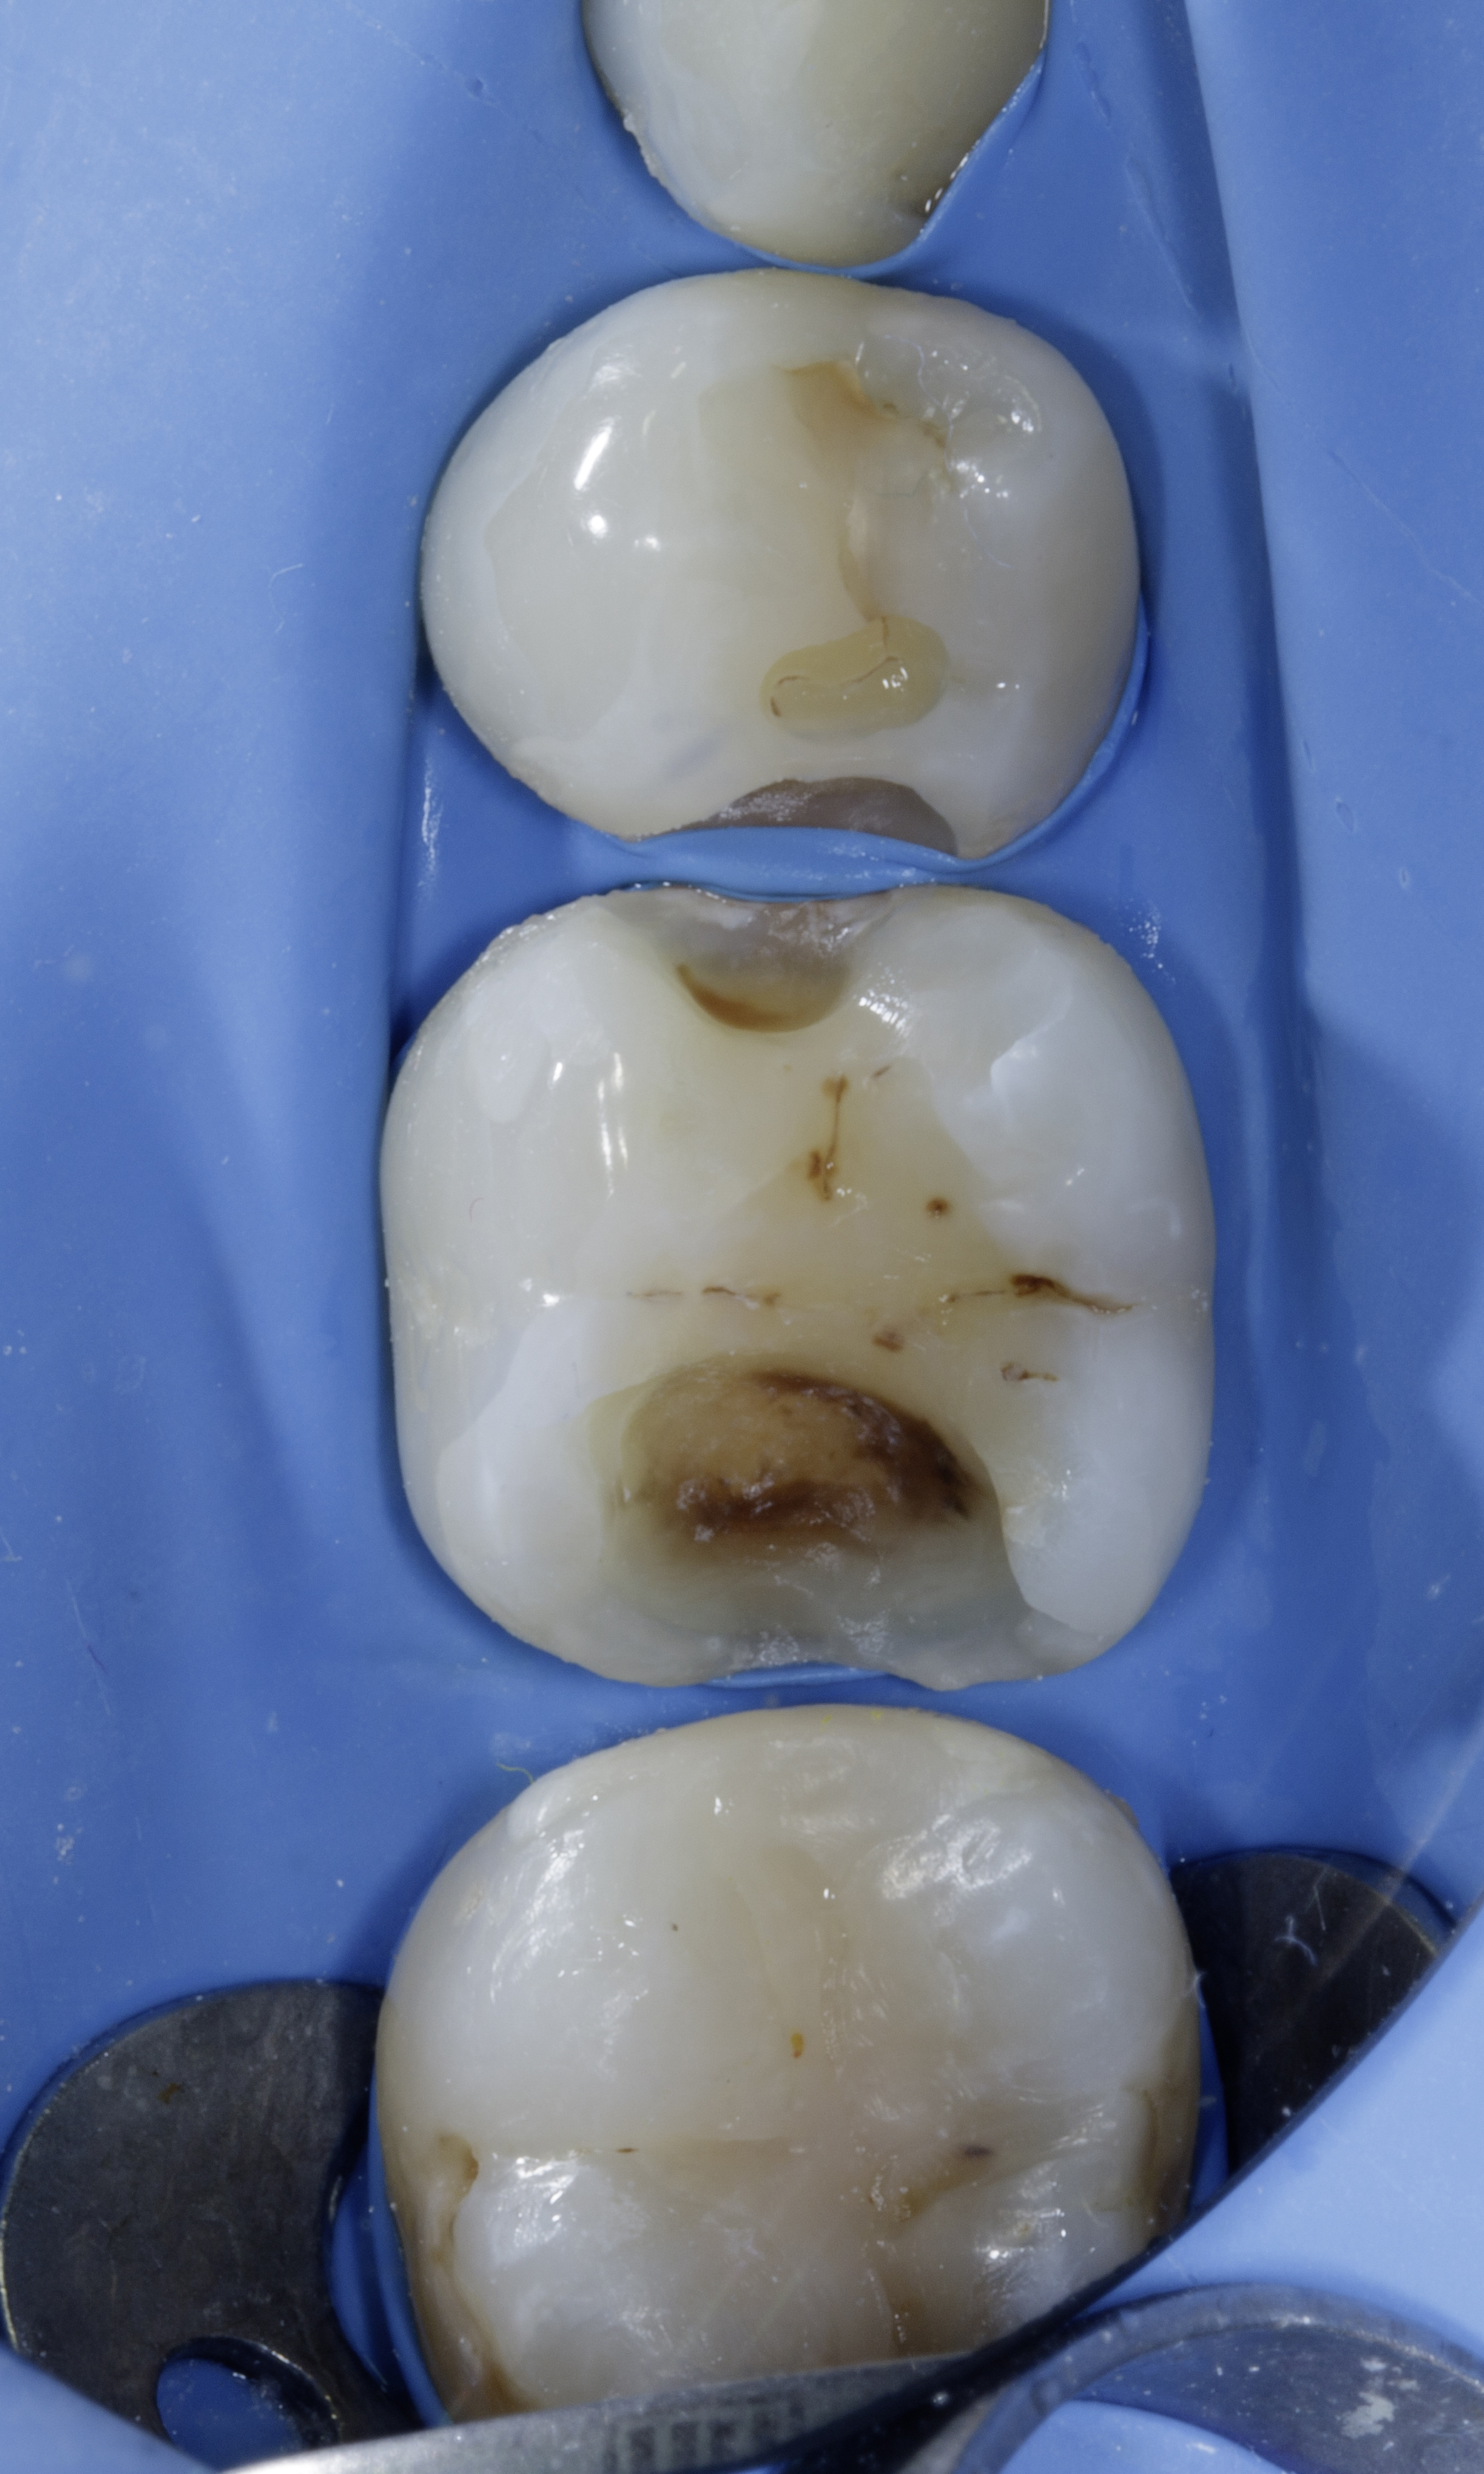

A 28-year-old woman presented to our office with complaints of sensitivity to cold temperatures and food impaction in her lower right quadrant. Her dental history revealed previous orthodontic treatment and multiple restoration failures in the same quadrant over the past 8-12 years.

Clinical examination showed significant mesio-occluso-distal (MOD) defects and Class 2 affecting teeth from #45 to #48.

Tooth #45: A distal carious lesion is suspected, potentially secondary to the adjacent mesial defect observed on tooth #46. No existing restoration is noted in this region, however, early discoloration and anatomical concavity suggest demineralization.

Tooth #46: Clinical examination revealed a mesial proximal carious defect with complete loss of the marginal ridge. On the distal aspect, an old composite restoration was observed, appearing underfilled and extended onto the occlusal surface. Evident marginal leakage and localized chipping were present along the restoration interface. Additionally, unsupported enamel was noted on the distobuccal cusp, indicating structural compromise and the risk of cusp fracture.

Tooth #47: An existing occlusal composite restoration demonstrated marginal discoloration and leakage. The distal surface exhibited a composite material of a different shade and texture, suggestive of a restoration placed at a later date. Lack of a defined marginal ridge resulted in an improper proximal contact. On the mesial surface, dark discoloration contiguous with the existing mesial pit composite indicated the presence of a recurrent or active Class II carious lesion.

Tooth #48: The mesial aspect showed dark discoloration extending into the existing mesial pit composite restoration, consistent with a developing or recurrent Class II carious lesion.

Bitewing radiograph confirmed the presence of multiple MOD / Class II carious lesions corresponding to the clinical findings. None of the defects demonstrated radiographic proximity to the pulp.

Figure 1. Multiple defects starting from tooth #45 to #48 as described above.Figure 2. Multiple class 2 defects starting from tooth #45 to #48 with loss of ideal contacts and contours.